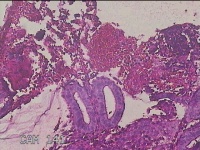

子宫腔组织

性别

女

年龄

47岁

临床诊断

异常子宫出血

一般病史

月经周期经期延长,月经量增多7天,超声提示子宫内膜11mm,回声不均。

标本名称

大体所见

灰白暗红色不规则碎组织1.5x1.3x0.3cm一堆。

图1

子宫内膜增生症。